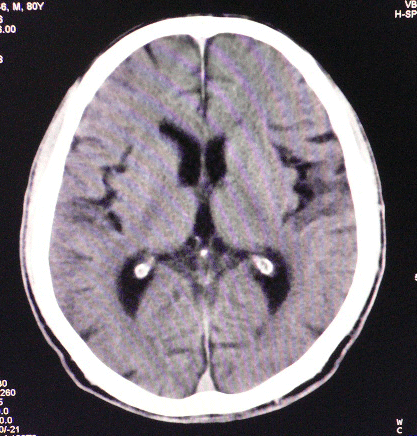

以下是引用狙击手在2007-4-8 22:45:00的发言:[br]出血?从患者的症状考虑病灶应该在左侧大脑半球的基底节区或颞顶部,如此小的病灶引起上述症状的可能性不大,患者可能有梗塞(时间短,目前ct还看不见)或是tia发作,再者像这样的线条形出血的确不多见,但还是有可能的,曾经碰到有外伤类似出血,复查后消失,所以还是慎重一点,短期复查即可。

以下是引用dyqct在2007-4-8 16:25:00的发言:[br]支持左侧放射冠区少量出血。